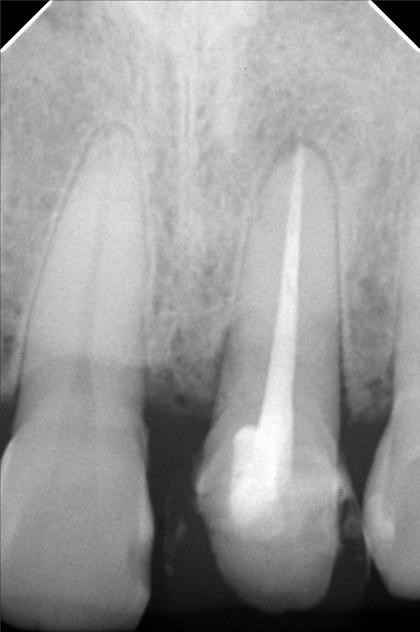

- Procedure